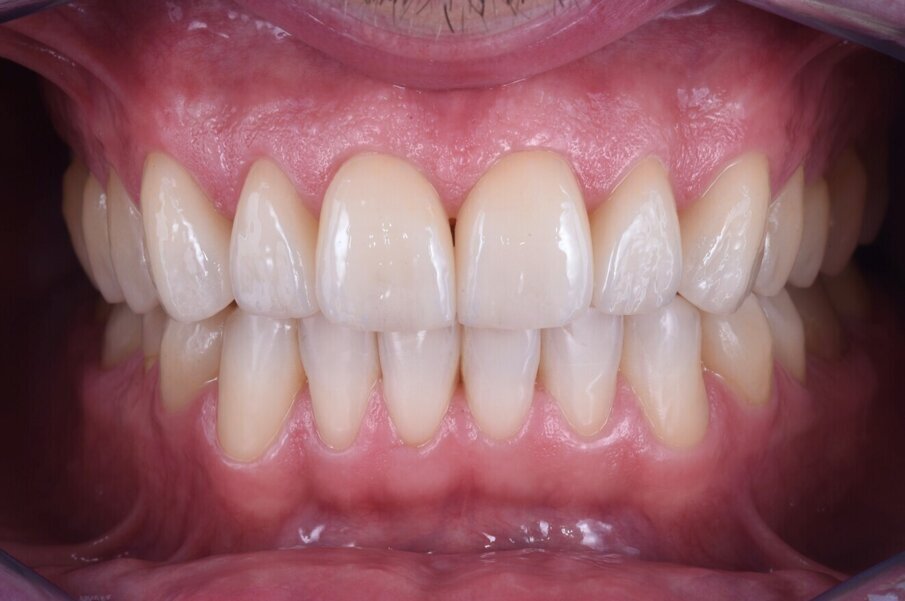

Nakonec byly finální korunkové náhrady (obr. 14) adhezivně fixovány v ústech za izolace kofferdamem (obr. 15). Pacient byl sledován několik týdnů po cementaci náhrad (obr. 16 a 17).

Obr. 16a: Závěrečná extraorální fotografie.

Obr. 16b: Závěrečná extraorální fotografie.

Obr. 17a–c: Finální intraorální fotografie.